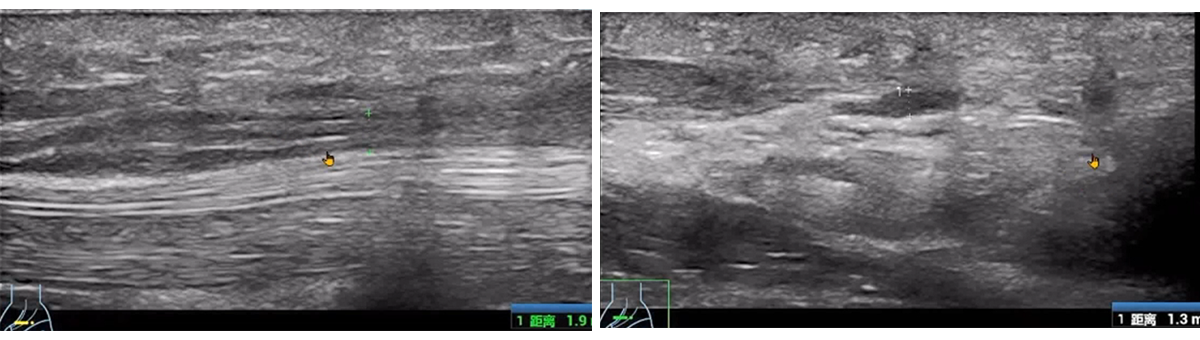

The patient experienced significant pain during wrist extension, indicative of "wrist drop."

Ultrasound revealed a "sandglass" or "sausage-like" change in the radial nerve, confirming nerve compression.

Such detailed imaging results are often critical for diagnosing and managing conditions like wrist drop, making POCUS (Point-of-Care Ultrasound) an invaluable tool in clinical practice.